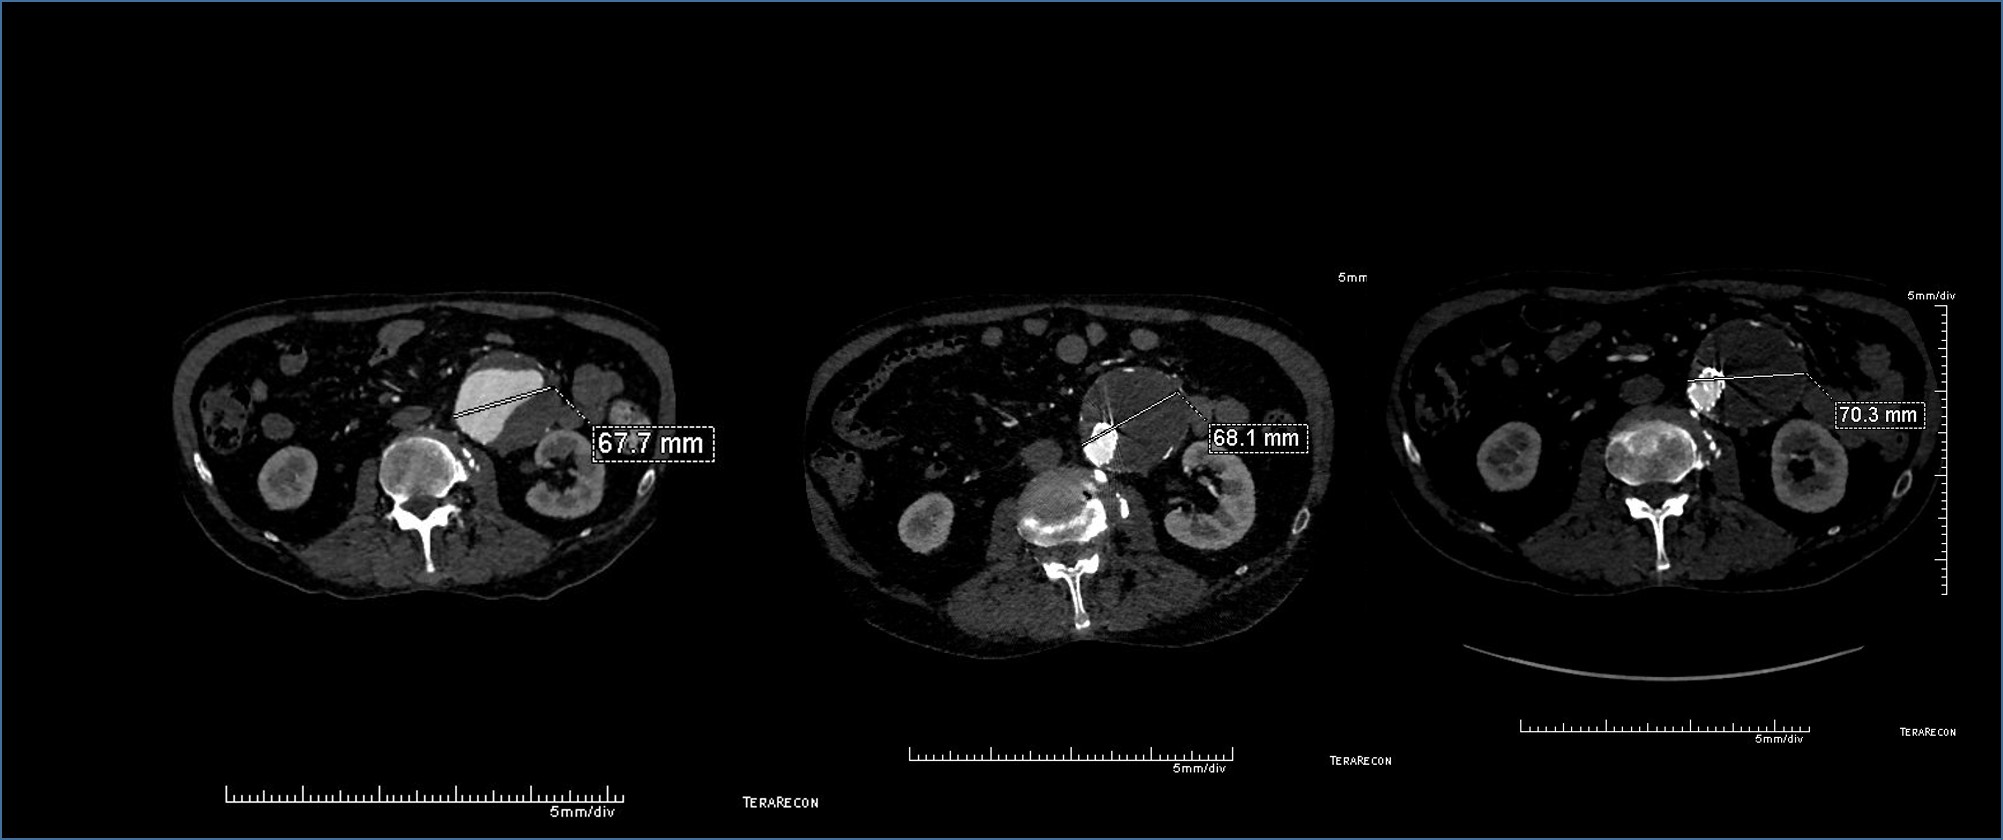

The patient had a successful EVAR or an eccentric infrarenal AAA which in followup grew due to the presence of a type II endoleak from the inferior mesenteric artery. This was seen on the CTA and duplex ultrasound. Planning for assessment and treatment involved analyzing the CTA in centerline, tracking the source of the arterial blood flow into the sac.